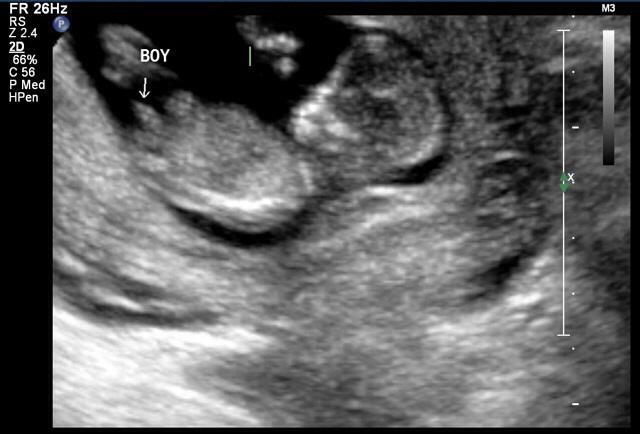

12 week scan potty shot. Sonographer adamant on gender

12 week scan potty shot. Sonographer adamant on gender from www.genderdreaming.com

Had our 12 week ultrasound today!! I just had my 20 week u/s and they said it was a girl. Nub method has very high accuracy when measuring angle of nub compared to spine! He is measuring at 5.5 pounds. I have two boy's, so i'm skeptical. 12 week ultrasound gender ultrasound gender prediction pregnancy gender reveal pregnancy goals pregnancy photos baby photos 12 week scan how to 'predict' baby's gender from an early ultrasound. How our 12 week ultrasound showed baby's gender! You must also remember that a nub analysis before 12 weeks of pregnancy, especially for babygram can give you a reliable prediction of your baby's gender.

Male gender may already be reliably determined when crl ≥ 55 mm (gestational age ≥ 12+0).

My mom bawled her eyes out and you can hear. 11 week ultrasound gender prediction november 2019 birth. Nub method has very high accuracy when measuring angle of nub compared to spine! Predictions made by sonographers during routine obstetric ultrasound. 12 week ultrasound gender ultrasound gender prediction pregnancy gender reveal pregnancy goals pregnancy photos baby photos 12 week scan how to 'predict' baby's gender from an early ultrasound. A theory that really works, here's how to use your scan to predict your baby's gender. 12 week ultrasound gender prediction mp3 & mp4. 19 week gender scan accuracy. Experts at babygram use the nub theory to thoroughly analyze your ultrasound. 12 weeks 5 days ultrasound/ gender reveal. We do this using the nub method! Ultrasound and gender detection gender is determined by visually inspecting the ultrasound several studies have been conducted to determine the accuracy of gender prediction at different at 12 weeks, 99% of male gender predictions were correct, and 91% of female predictions were. You mentioned that you're 12 weeks along.